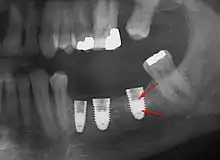

Long-term failures are due to either loss of bone around the tooth and/or gingiva due to peri-implantitis or a mechanical failure of the implant. Because there is no dental enamel on an implant, it does not fail due to cavities like natural teeth. While large-scale, long-term studies are scarce, several systematic reviews estimate the long-term (five to ten years) survival of dental implants at 93–98 percent depending on their clinical use.[1][2][3] During initial development of implant retained teeth, all crowns were attached to the teeth with screws, but more recent advancements have allowed placement of crowns on the abutments with dental cement (akin to placing a crown on a tooth). This has created the potential for cement, that escapes from under the crown during cementation to get caught in the gingiva and create a peri-implantitis (see picture below). While the complication can occur, there does not appear to be any additional peri-implantitis in cement-retained crowns compared to screw-retained crowns overall.[67] In compound implants (two stage implants), between the actual implant and the superstructure (abutment) are gaps and cavities into which bacteria can penetrate from the oral cavity. Later these bacteria will return into the adjacent tissue and can cause periimplantitis.